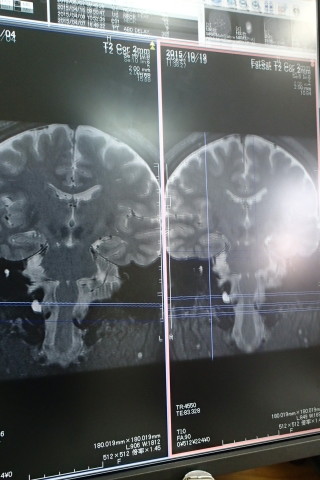

今日、実は半年ぶりの検査でした。

検査の結果は良好でした!

変化無しなのでよしとしよう!

良性なので大丈夫!だそうです。

写真を撮ったら、プリントアウトしてくれた。

医院長先生!ありがとうございます!